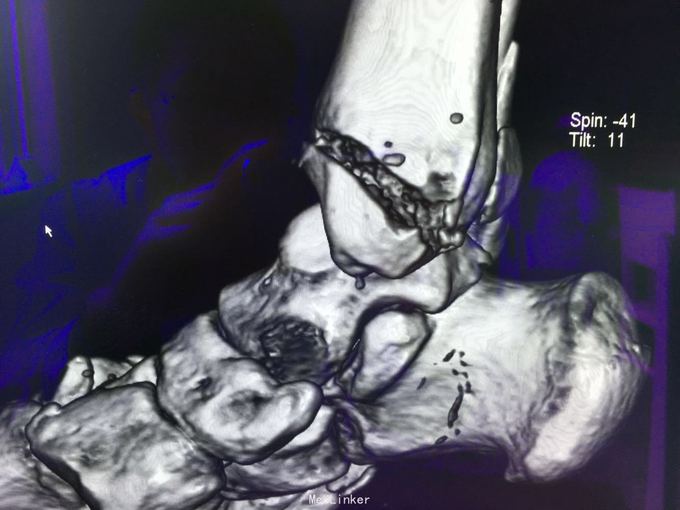

查体:左肾区叩痛,无皮肤隆起,未扪及肿块;腰椎压痛,活动受限,双下肢感觉存在,右小腿石膏托外固定,有踝关节明显肿胀,局部压痛活动受限,指端感觉血运可。 CT及X片:L2、L4椎体爆裂性骨折,L1-L4左侧横突骨折,右坐骨支骨折,右侧胫骨内、后及右侧腓骨外踝骨折,右足第1-4跖骨向外侧脱位及半脱位,伴近端斯脱性骨折。左肾挫裂伤,左肾重度积水,左肾周血肿。

诊断:右足lisfrance损伤,左肾挫裂伤;左肾周血肿,左侧输尿管结石伴左肾重度积水,L2、L4椎体骨折,L1-L4左侧横突骨折,右侧坐骨支骨折,右三踝骨折,全身多处皮肤软组织挫伤 处理:急诊行左肾探查,左肾切除术,择期行经后路腰2、4椎体骨折切开复位、椎公根螺钉内固定术+右内、外踝骨折切开复位内固定术,择期行右足lisfrance关节复位克氏针内固定术。